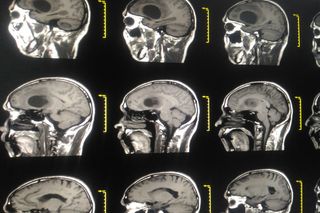

Glioblastoma is the diagnosis no one wants to get. Due to its rapid and invasive growth, combined with resistance to common forms of treatment, this most aggressive form of brain cancer often leaves patients with only a few months to live.

The tumor ecosystem is highly complex and difficult to target. Many drugs cannot enter the brain through the tight blood–brain barrier, and even if treatment — like chemo- or radiotherapy — is possible, the brain environment is extremely sensitive and has only limited ability to recover.